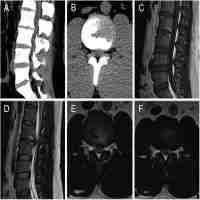

A case of intradural lumbar disc herniation.